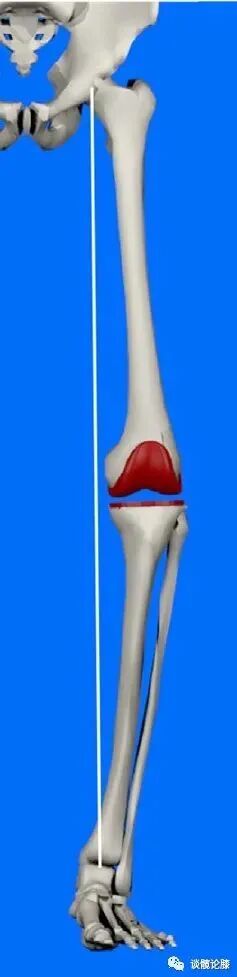

机械对线技术【Mechanical Alignment (MA) technique】 MA技术,即股骨远端和胫骨近端截骨面均垂直机械轴线,使下肢轴线与关节线垂直。

改良机械对线技术【Adjusted Mechanical Alignment (aMA) technique】aMA技术,即对严重冠状面畸形时,术中容许残留轻-中度畸形。利用股骨侧截骨调整下肢力线,而胫骨截骨面仍垂直胫骨机械轴。

限制性动力对线技术【Restricted Kinematic Alignment (rKA) technique】有学者认为KA技术仅适用于轻度冠状面畸形(≤3º),且关节线倾斜度小于5°(此角度为力线安全区)的情况,当冠状面畸形(主要为患者关节炎前即存在中重度冠状面畸形)超过这一范围时则宜采用rKA技术。

具体方法为:rKA技术遵循KA技术的主要技术原理,即尽可能保存股骨假体的运动对线,通过胫骨侧截骨调整下肢力线和关节线倾斜度,避免冠状面畸形及关节线倾斜度超过安全区。